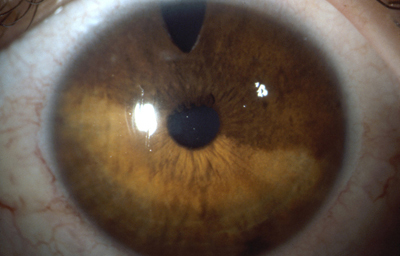

Aniridia completa, catarata y distrofia corneal de la aniridia

Archivo Dr. Francisco Barraquer

Caso de paciente con Coloboma en un ojo y Aniridia en el contralateral

OD

Archivo Fotográfico Dr. Francisco Barraquer

OI

Archivo Dr. Francisco Barraquer